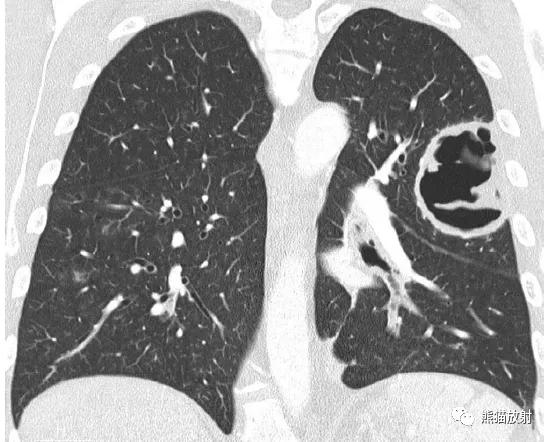

↑ 肺脓肿 Lung abscess

35岁男性,高热,大量浓痰。痰培养铜绿假单胞菌阳性。CT示左肺上叶的大空洞,空洞内见粗大分隔。